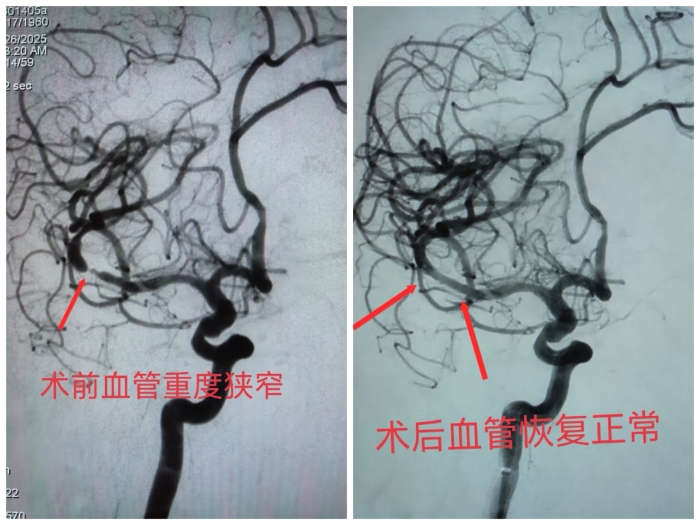

手术当天,在数字减影血管造影系统的精确引导下,神经内科团队如履薄冰又沉稳有序地操作,将一枚微小而柔软的支架精准植入狭窄的血管段。顷刻之间,原本狭窄的血管被成功扩张,血流恢复通畅,大脑供血立时改善。整个手术过程顺利,患者全程保持清醒状态。

经过神经内科团队的细致检查与综合评估,病因终于浮出水面——患者右侧大脑中动脉存在严重狭窄。这条血管是脑部血供的“生命主干道”,一旦完全堵塞,将引发大面积脑梗死,可能导致永久性偏瘫、言语障碍,甚至危及生命。患者此前出现的短暂性肢体无力,正是大脑严重缺血、脑梗死一触即发的危险征兆。